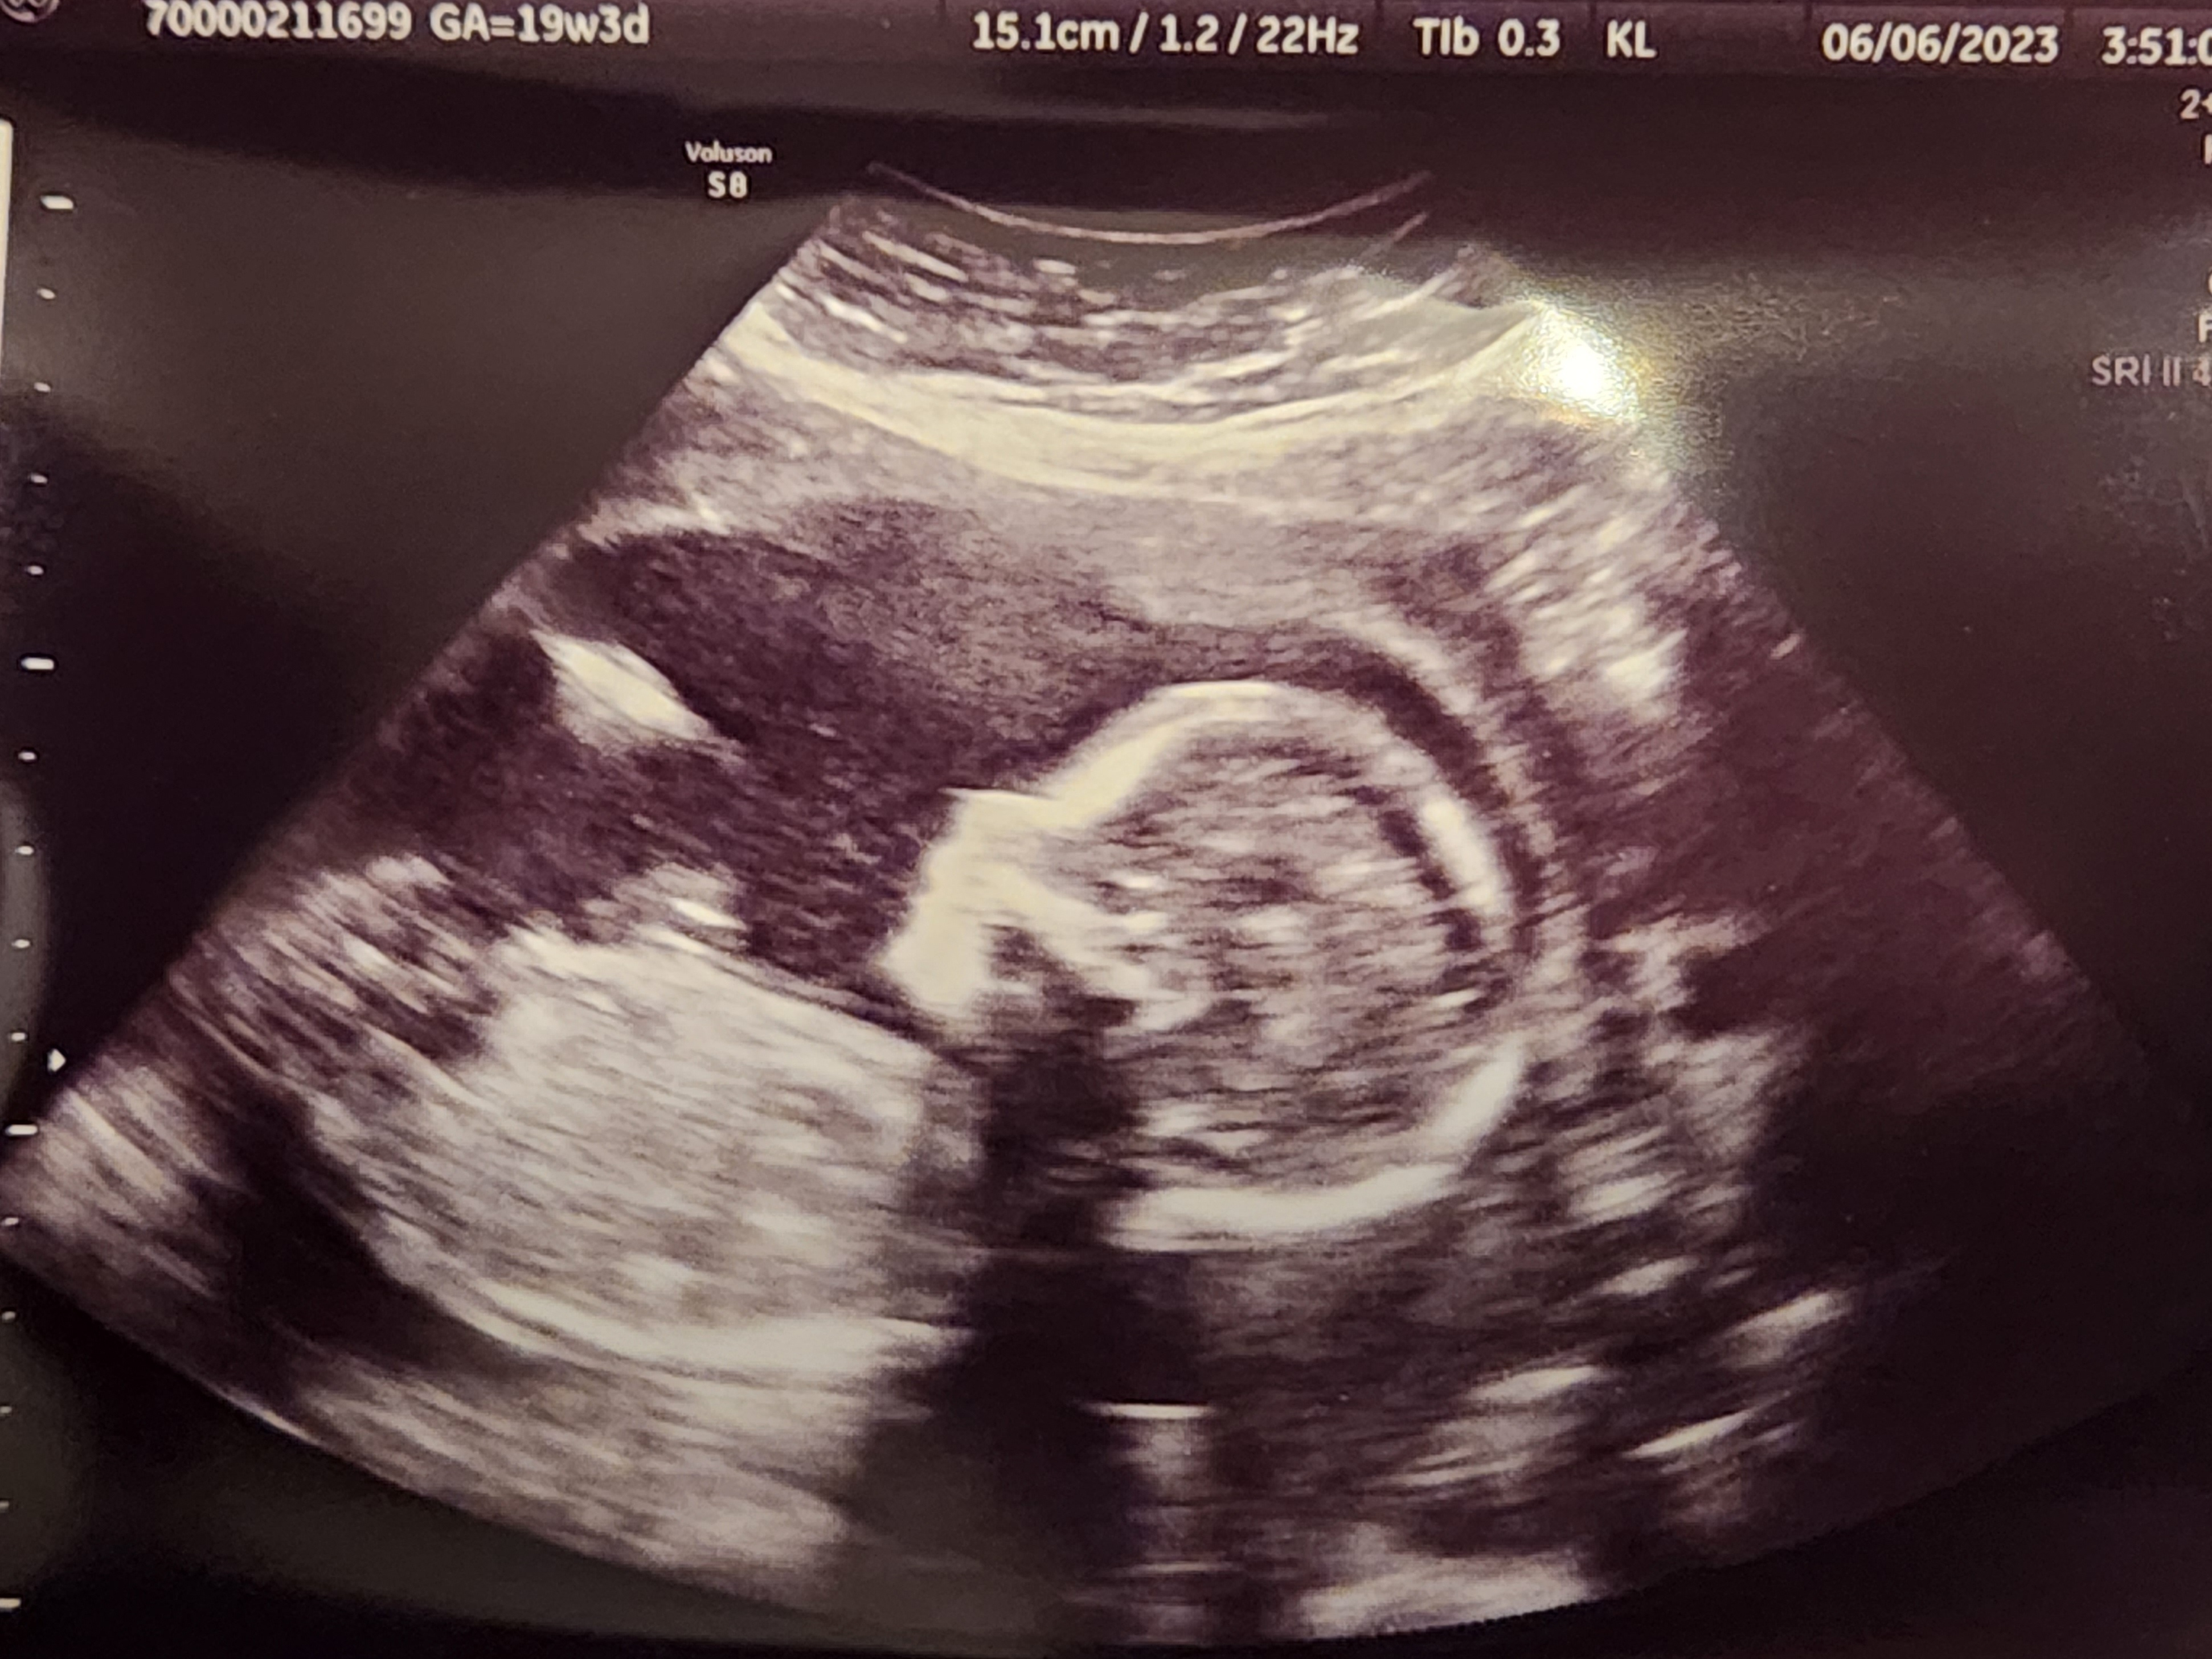

Re: Ultrasound Thread

mizzoumomma11

member

June 2023

Baby girl says, “All good in here!” 👍

🤣🥰🥰